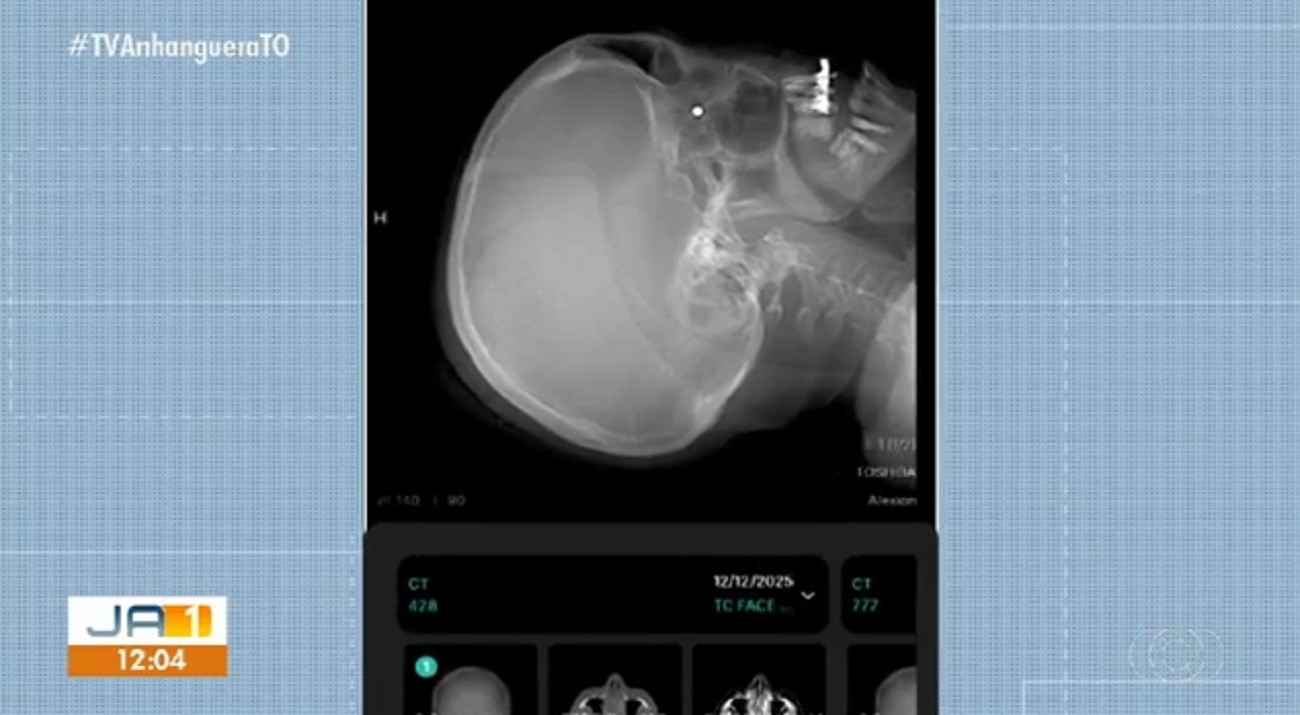

Exames de raio-X confirmaram que o chumbinho está atrás do globo ocular. Segundo a filha, Agnes Rocha, a mãe passou por quatro oftalmologistas e todos recomendaram não retirar o chumbinho por enquanto. “Graças a Deus ela não está sentindo nenhuma dor desde o momento que ela foi acertada até depois da cirurgia, ela não não sentiu dor na no olho”, contou.

Raio-X mostra projétil atrás do globo ocular de Isabel Cristina Rocha

TV Anhanguera/Reprodução